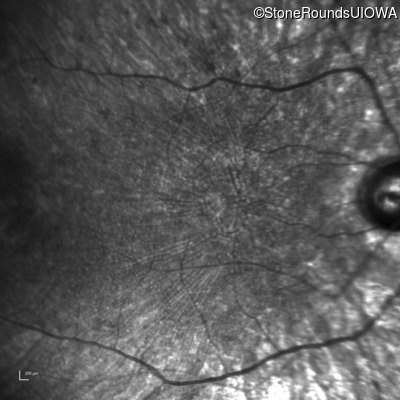

This 21 year old man first had difficulty seeing the blackboard in the 5th grade. Two years later he began having difficulty seeing in dim light. In high school he was approximately 50 pounds overweight, but was able to lose that weight with a strict diet.

| Bardet Biedl Syndrome | BBS1 | Met390Arg ATG>AGG | Arg277Lys AG(G)>AA(G) | AR |